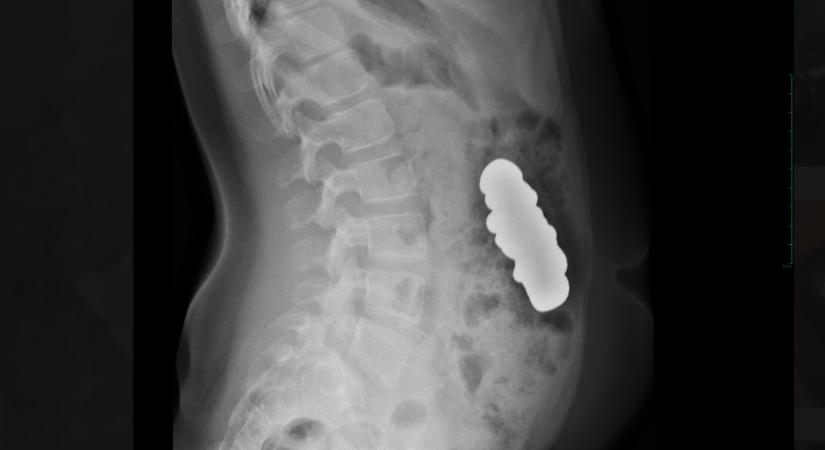

Húsz mágnest nyelt le egy gyerek Ma 15:45 Civishír Ágnes Gyerek Budapesten operálták meg. Elolvasom a cikket >> - Hirdetés -